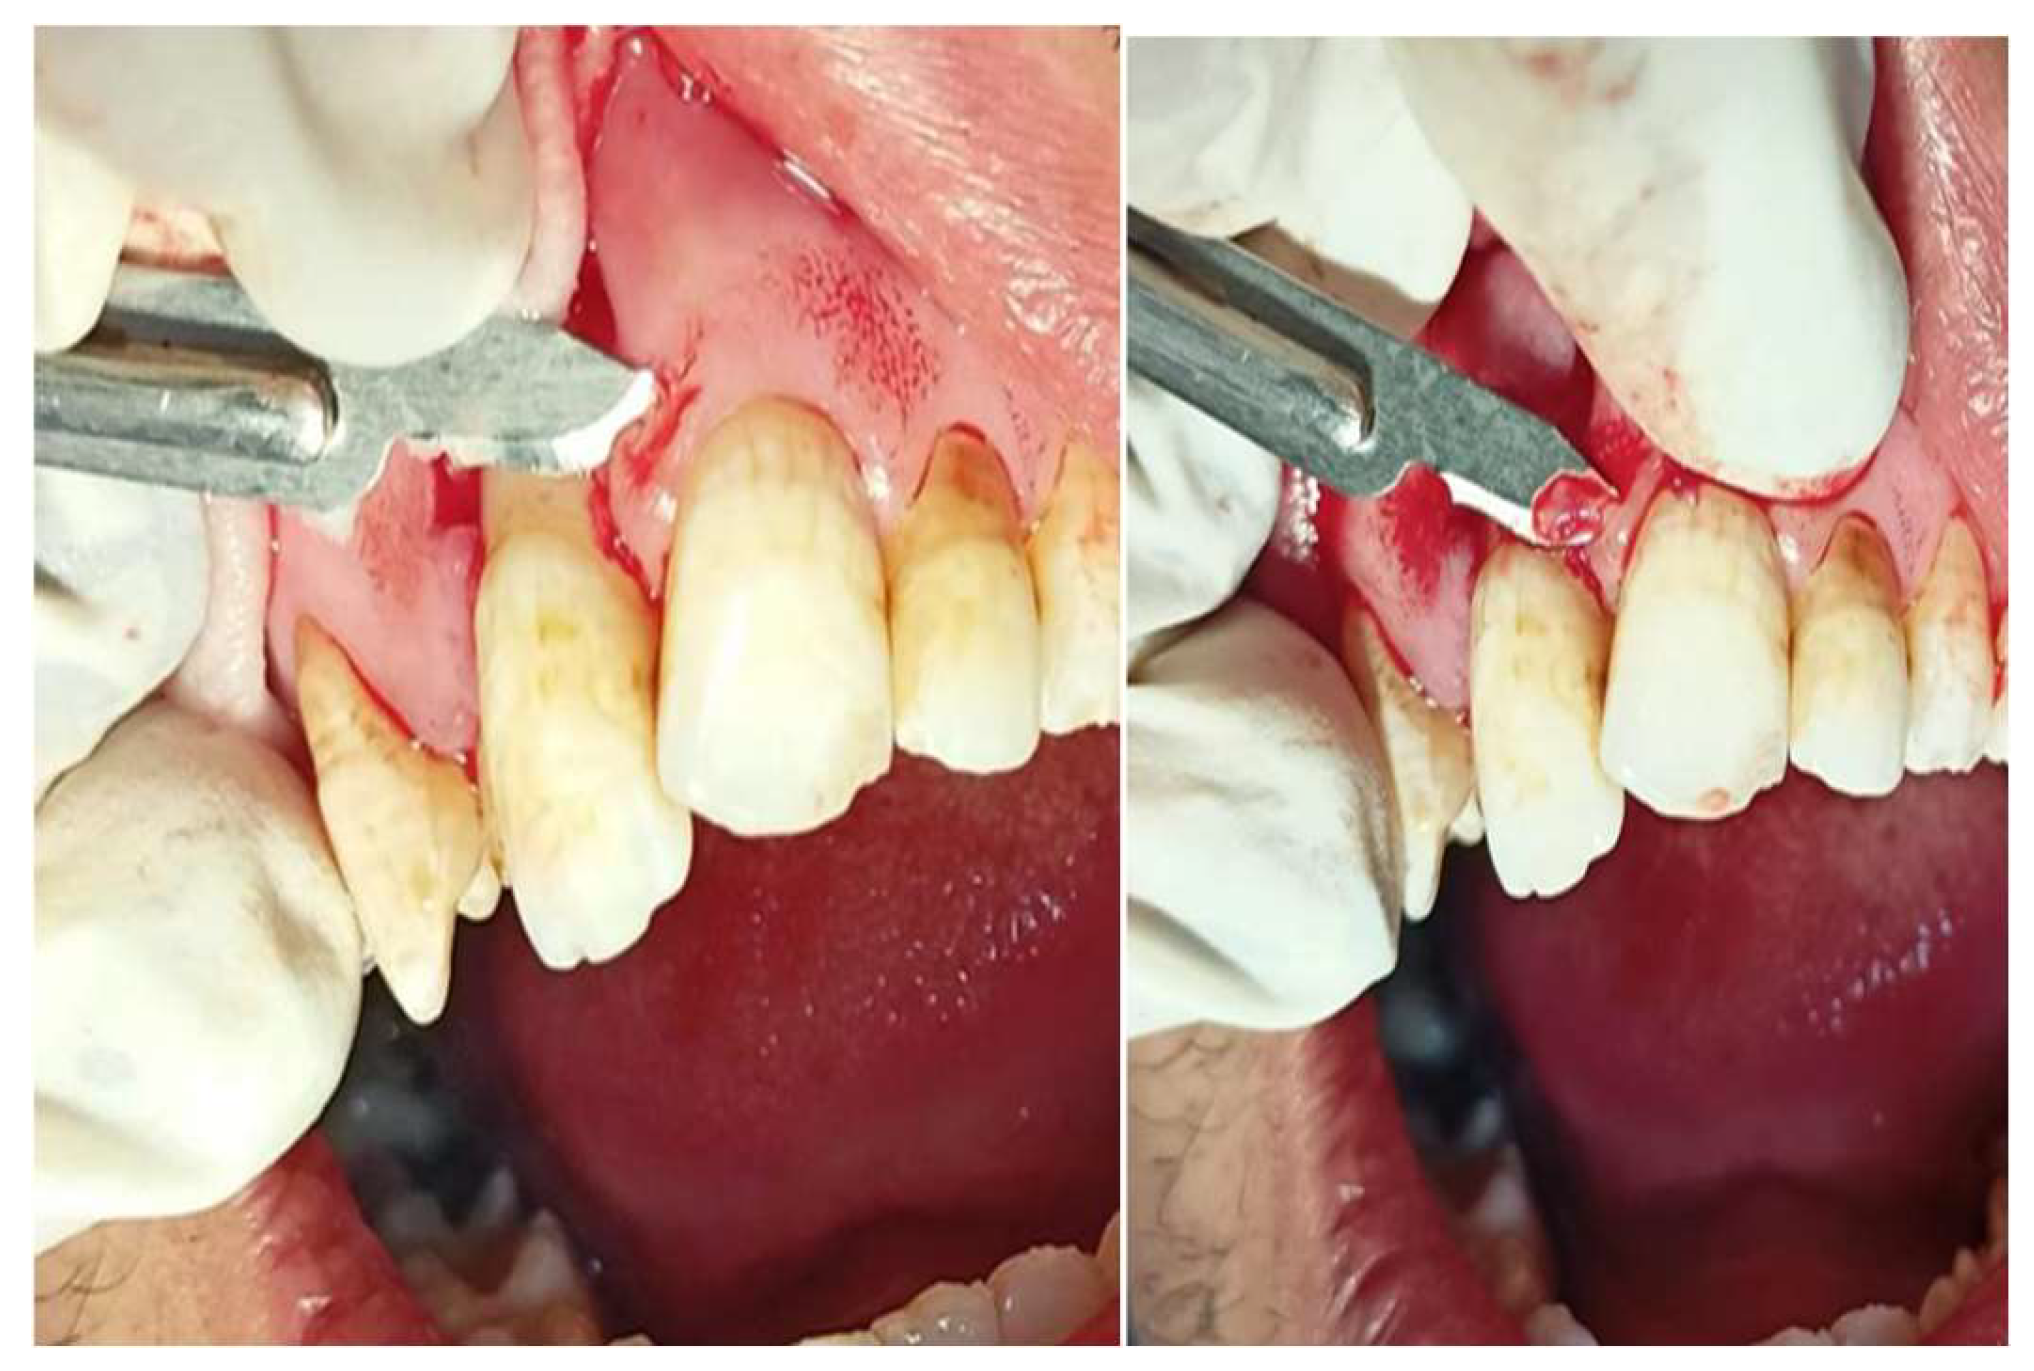

Fig3. Coronal Advancement flap horizontal incision.

Figure 4. vertical incision.

Figure 5. incisions of CAF (trapezoid flap).

Preprints 139955 g020

Figure 6. advancement of flap coronally.

A sulcular incision is made around the first premolar, with horizontal incisions which are positioned at a distance from the tip of the anatomical papillae equal to the depth of the recession plus 1 mm. This horizontal incision will extend only 3mm, never extend to adjacent tooth.

Vertical incisions at the ends of the horizontal incision reach into the alveolar mucosa, facilitating deep, superficial partial split dissection needed for graft integration and contraction. A periosteal elevator is employed to elevate a full thickness flap, just apical to recession area, which is then trimmed apically, and root biomodification by EDTA is carried out up to the mucogingival junction to ready an appropriate bed for the graft.